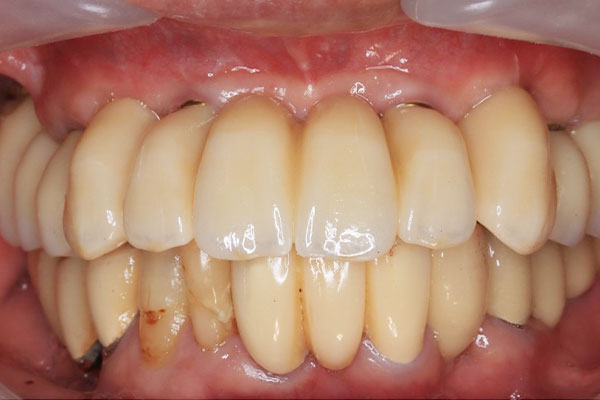

• 治療前

• 治療後

上顎6本、¥3,283,500

義歯を使用し、残存歯も保存不可能だった患者に対し、6本のインプラントを用いて伵合を回復した症例。